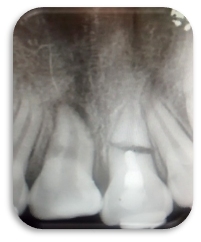

Se apreció lesión apical en la pieza 2.1 (imagen 1). Al realizar el acceso con una fresa bola de tallo largo #6 se tomó la radiografía de cavometría con la lima Flex R #20 a 20 mm (imagen 2), posteriormente se colocó pasta de hidróxido de calcio y se dejó durante un mes, después se tomó la radiografía de cronometría con cono #55. Se realizó la técnica de Crown Down para limpiar la parte coronal. Se instrumentó a partir de la lima #20 hasta la lima #55 master a 20 mm y se realizó retroceso hasta la lima #80. Al término del tratamiento se usó la técnica de condensación lateral combinada con vertical de gutapercha (imagen 3).

Imagen 1

Imagen 2

Imagen 3

Imagen 4